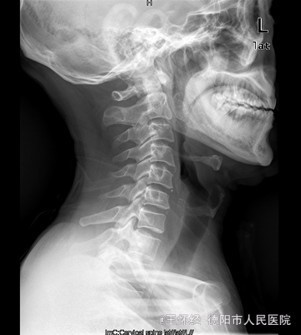

患者男,52岁,因“车祸伤后右肩部、右胸壁疼痛伴右上肢活动障碍1+天”入院。入院1+天前,患者因车祸伤致右肩部疼痛、有胸壁疼痛、右上肢活动障碍、无法上抬,无明显麻木,右胸锁关节处可见一明显隆起硬块、压痛明显,同时自觉少许呼吸困难,我院急诊行X光片示“右胸锁关节脱位”,遂收住我科。

查体:右侧胸锁关节处叩压痛明显,可扪及一隆起、质硬,右侧胸壁乳头周围肿胀,右肩外展因胸锁关节处疼痛而受限受限。 辅查:X片及CT提示示右侧胸锁关节向前脱位、双侧第一肋骨骨折

初步诊断:车祸伤:1.右侧胸锁关节前脱位;2.双侧第一肋骨骨折。 诊疗计划:右侧胸锁关节脱位切开复位,锚定固定修复关节囊及周围韧带。